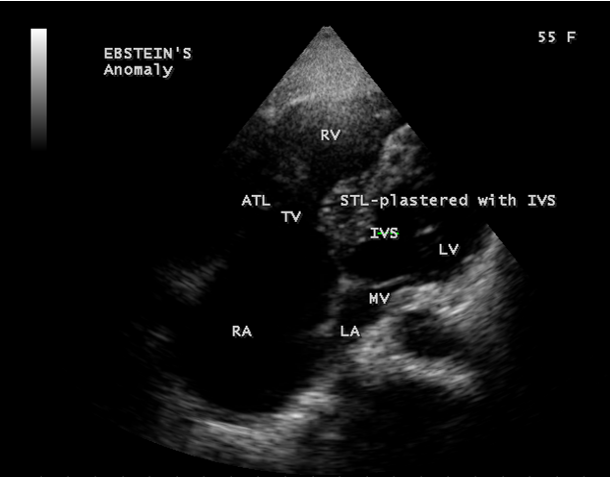

A 55-year old asymptomatic, acyanotic female, given birth to three children, presented with grade 2/6 systolic murmur at the lower left sternal border. 2D echocardiography revealed a septal tricuspid leaflet tethering and a high moderate tricuspid regurgitation as shown in Figures 9 and 10 suggesting an Ebstein’s anomaly.

The anterior tricuspid leaflet is not involved in the process of downward displacement, it may be abnormally inserted occasionally and Shiina, et al documented the apical displacement of anterior tricuspid leaflet in 14% of cases echocardiographically [39]. The anterior leaflet forms a large, sail-like intracavitary curtain as in Figures 14, 25 and contains muscular strands instead of consisting entirely of a fibrous membrane as in the normal tricuspid valve [40]. It is potentially mobile with a brisk sail-like movement as shown in Figure 21 to 24 [41], free bloating with a ‘whipping motion’ across the right ventricular outflow tract (RVOT) as shown in Figure 26 and in some cases, the movement is restricted due to its adherence to the ventricular wall as in Figure 1 and 2, 4 and 9. It is often fenestrated, may in part be musculaized , inserting into the trabeculations of the right ventricle (RV) as in Figure 28 and rarely, the anterior leaflet forms an ‘atretic’ membrane that spans the midportion of the right ventricular cavity as in Figure 16.

The tricuspid orifice is typically incompetent as in Figures 3, 5 and 10, occasionally stenotic, and rarely imperforate as in Figure 16 [44],[45]. The true anatomic tricuspid annulus occupies its normal position at the right atrioventricular junction and it is less well defined than in a normal heart. The annulus tends to be appreciably dilated and contribute to the development of valvular incompetence. In extreme downward displacement of posterior and septal leaflets, the closure of the tricuspid annulus depends on the size and potential excursion of anterior leaflet. When the chordal attachments are short and the leaflets contain multiple or large fenestrations, adequate valve closure is impossible to achieve and varying degrees of regurgitation results. Color flow imaging and Doppler interrogation can establish the relatively low velocity regurgitant flow as in Figure 6, which begins at the level of the displaced septal and posterior leaflets as in Figures 5 and 10 and courses through the atrialized right ventricle into the right atrium proper as shown in Figure 5. Tricuspid regurgitation increases by annular dilatation [46]. During contraction of the atrium, the atrialized portion of the right ventricle balloons out and acts as a passive reservoir. Functional improvement of right ventricle depends on the severity of tricuspid regurgitation and on the ratio of the combined areas of right atrium and atrialized right ventricle relative to the areas of functional right ventricle and left ventricle [47]. Celermajer, et al described an echocardiographic grading score for neonates with Ebstein’s anomaly as shown in the Table 5 [48].